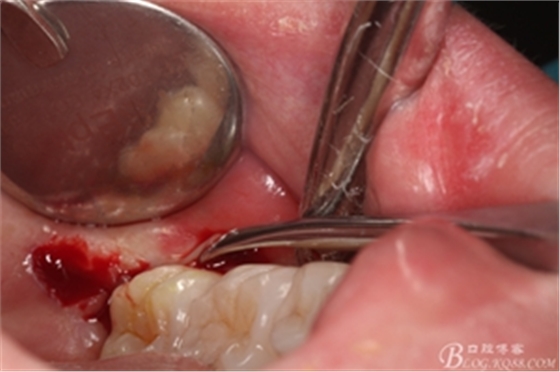

圖10. 翻開(kāi)瓣。38牙冠還有部分骨質(zhì)覆蓋,遂用高速牙鉆去骨

圖11.去骨---暴露出38的牙冠最大周徑